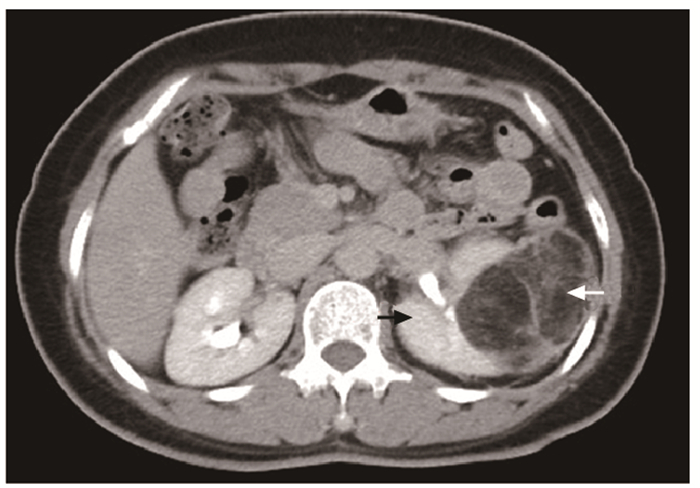

结果   14例AML患者中有1例相对孤立肾合并AML、7例多发AML、8例巨大AML(肿瘤最大直径>7 cm)、6例紧邻肾集合系统或肾门的AML以及2例合并出血破裂史AML, 病情复杂, 手术难度大。采取经腹腔镜或开放肾部分切除或肿瘤剜除术后, 顺利切除肿瘤, 病理检查提示肾AML, 术后定期门诊随访, 行CT扫描均无复发。全部患者术后肾功能保持良好, 术前和术后1个月血肌酐水平分别为(84.1±26.8)μg/ml和(97.5±37.0)μg/ml, 两组数据差异无统计学意义(t=-3.193, P>0.05)。

Results  Among 14 patients with renal AML, 1 had a relative solitary kidney with AML, 7 had multiple AML, 8 had huge AML (the maximum diameter of the tumor >7 cm), 6 had AML adjacent to the renal collection system or the renal portal, and 2 had AML combined with bleeding and rupture history; all cases were complicated and difficult to treat. All operations were successfully performed by laparoscopic or open partial nephrectomy or enucleation of the tumor, and pathological examination indicated renal AML. All patients were regularly followed up and no recurrence was found by CT scanning. The renal function of all patients was well preserved; the concentration of serum creatinine before and 1 month after the operation were (84.1±26.8)μg/ml and (97.5±37.0)μg/ml respectively, without statistically insignificant difference (t=-3.193, P>0.05).